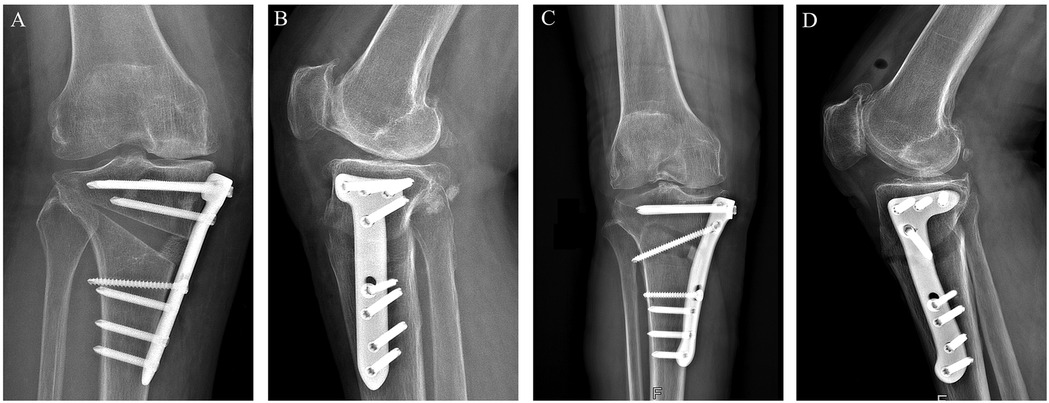

Background: High tibial osteotomy (HTO) corrects varus malalignment and unloads the medial knee compartment, yet the conventional T-shaped locking plate may cause discomfort due to suboptimal anatomic conformity. We developed a novel locking plate to improve anatomic fit and fixation stability and compared it with the T-shaped plate in Anterior Popliteus Transtibial-tuberosity high tibial osteotomy (APTT-HTO). Methods: This single-center retrospective observational comparative study included 14 consecutive patients who underwent APTT-HTO between August 2024 and June 2025. Patients were grouped by implant type (novel plate: n = 7; T-shaped plate: n = 7). Postoperative CT quantified plate orientation/position, plate–bone conformity (gap and position mismatch), screw alignment, and standard alignment parameters (hip–knee– ankle angle [HKA], posterior tibial slope [PTS]). Results: The novel plate showed more posteromedial placement and superior anatomic conformity. The plate angle relative to the posterior tibial condylar reference line was larger with the novel plate (74.49° ± 8.76°) than with the T-shaped plate (62.62° ± 7.05°, P<0.05). The proximal central screw–plate angle was smaller (5.70° ± 4.80° vs 27.48° ± 6.05°, P<0.05), the plate–bone gap was reduced (1.84 ± 0.68 mm vs 2.98 ± 0.38 mm, P<0.05), and plate position mismatch was lower (20.20% ± 7.70% vs 37.70% ± 10.00%, P<0.05). Proximal and distal offsets considered separately were not significantly different (P>0.05). Both groups achieved the planned coronal correction, and sagittal PTS remained stable (P>0.05). Conclusions: In this CT-based cohort, the novel anatomically contoured locking plate achieved superior anatomic conformity in APTT-HTO—characterized by more posteromedial positioning, a more favorable screw trajectory, and improved plate–bone apposition—compared with a conventional T-shaped plate. These findings warrant confirmation in larger, prospective studies.